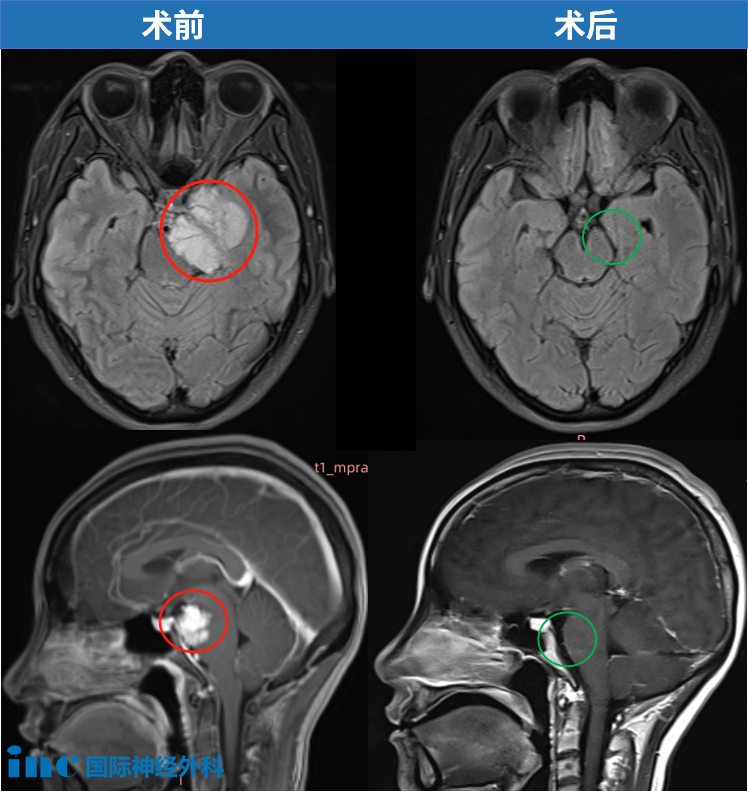

部分患者在偶然间检出巨大脑膜瘤。例如一位60岁患者,于偶然检查中发现鞍旁存在巨大脑膜瘤,且肿瘤已侵入海绵窦区域,但当时并未呈现任何临床症状。对于某些患者而言,当发现脑瘤且无伴随症状时,初步选择往往是定期观察。然而,鉴于该肿瘤的体积及其生长态势,继续等待已非适宜选择。

本次手术由INC国际神经外科顶尖专家主刀,过程极为顺利,实现了肿瘤的完全切除,同时完整保留了颈内动脉,海绵窦区域亦未予打开。术后磁共振成像显示良好结果。需要强调的是,位于鞍区、岩斜区或桥小脑角等关键区域的4厘米脑膜瘤,即便病理性质属于良性,其压迫视神经、脑干或重要颅神经的风险依然极高,加之手术操作本身较为复杂。因此,无论患者是否出现临床症状,此类肿瘤均应由神经外科医生进行系统而严谨的术前评估,并积极、及时地考量手术治疗方案,否则极可能导致不可逆转的神经功能损伤。